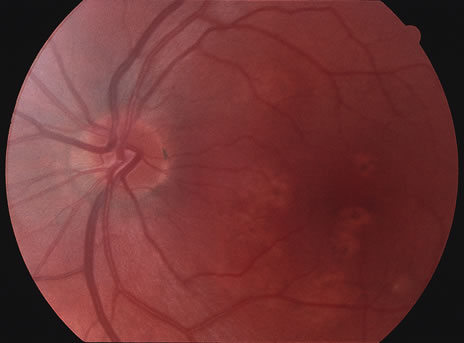

RETINAL FINDINGS

The fundus findings tend to depend on the chronicity of the disease. In new-onset cases, there are just a few choroidal lesions most of which are in the posterior pole. The newer lesions tend to be yellowish-white in coloration and with time they become punched-out. The size of the lesions can be variable ranging from one third to 1 disc diameter in size. They can become confluent and so they may appear larger than the typical size. The newer lesions are associated with visual distortions. Rarely subretinal fluid may be present over fresh choroidal lesions. In addition, choroidal neovascularization may be seen in one third of cases. Subretinal hemorrhage and subretinal fluid should be considered as signs of the development of a possible choroidal neovascular membrane. Retinal phlebitis is rarely present but may be seen as well (Fig. 9).

Fig. 9. A and B. Fundus photographs of the right and left eye showing the classic circular choroidal lesions with marked pigment clumping in a case of multifocal choroiditis.

Fluorescein angiography may show hyperfluorescent spots that increase slightly in the later phases in active lesions. In inactive lesions, these spots become window defects. If there is a choroidal neovascular membrane it is usually seen at the edge of the scar and tends to have classic features. ICG angiography shows hypofluorescent lesions some of which cannot be seen by fundoscopy or by fluorescein angiography. In addition, there may be hypofluorescence surrounding the optic disc in cases of enlarged blind spots in conjunction with multifocal choroiditis.42